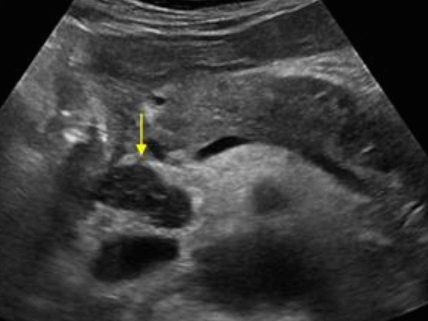

US finding

- 담낭관 또는 담낭 경부에 결석이 확인된다.

- 총간관(CHD) 또는 담낭관(cystic duct)의 확장소견이 보인다.

- 간내외 담관의 확장이 관찰된다.

Mirizzi's syndrom 담관암(Cholangiocarcinoma, CCCs)